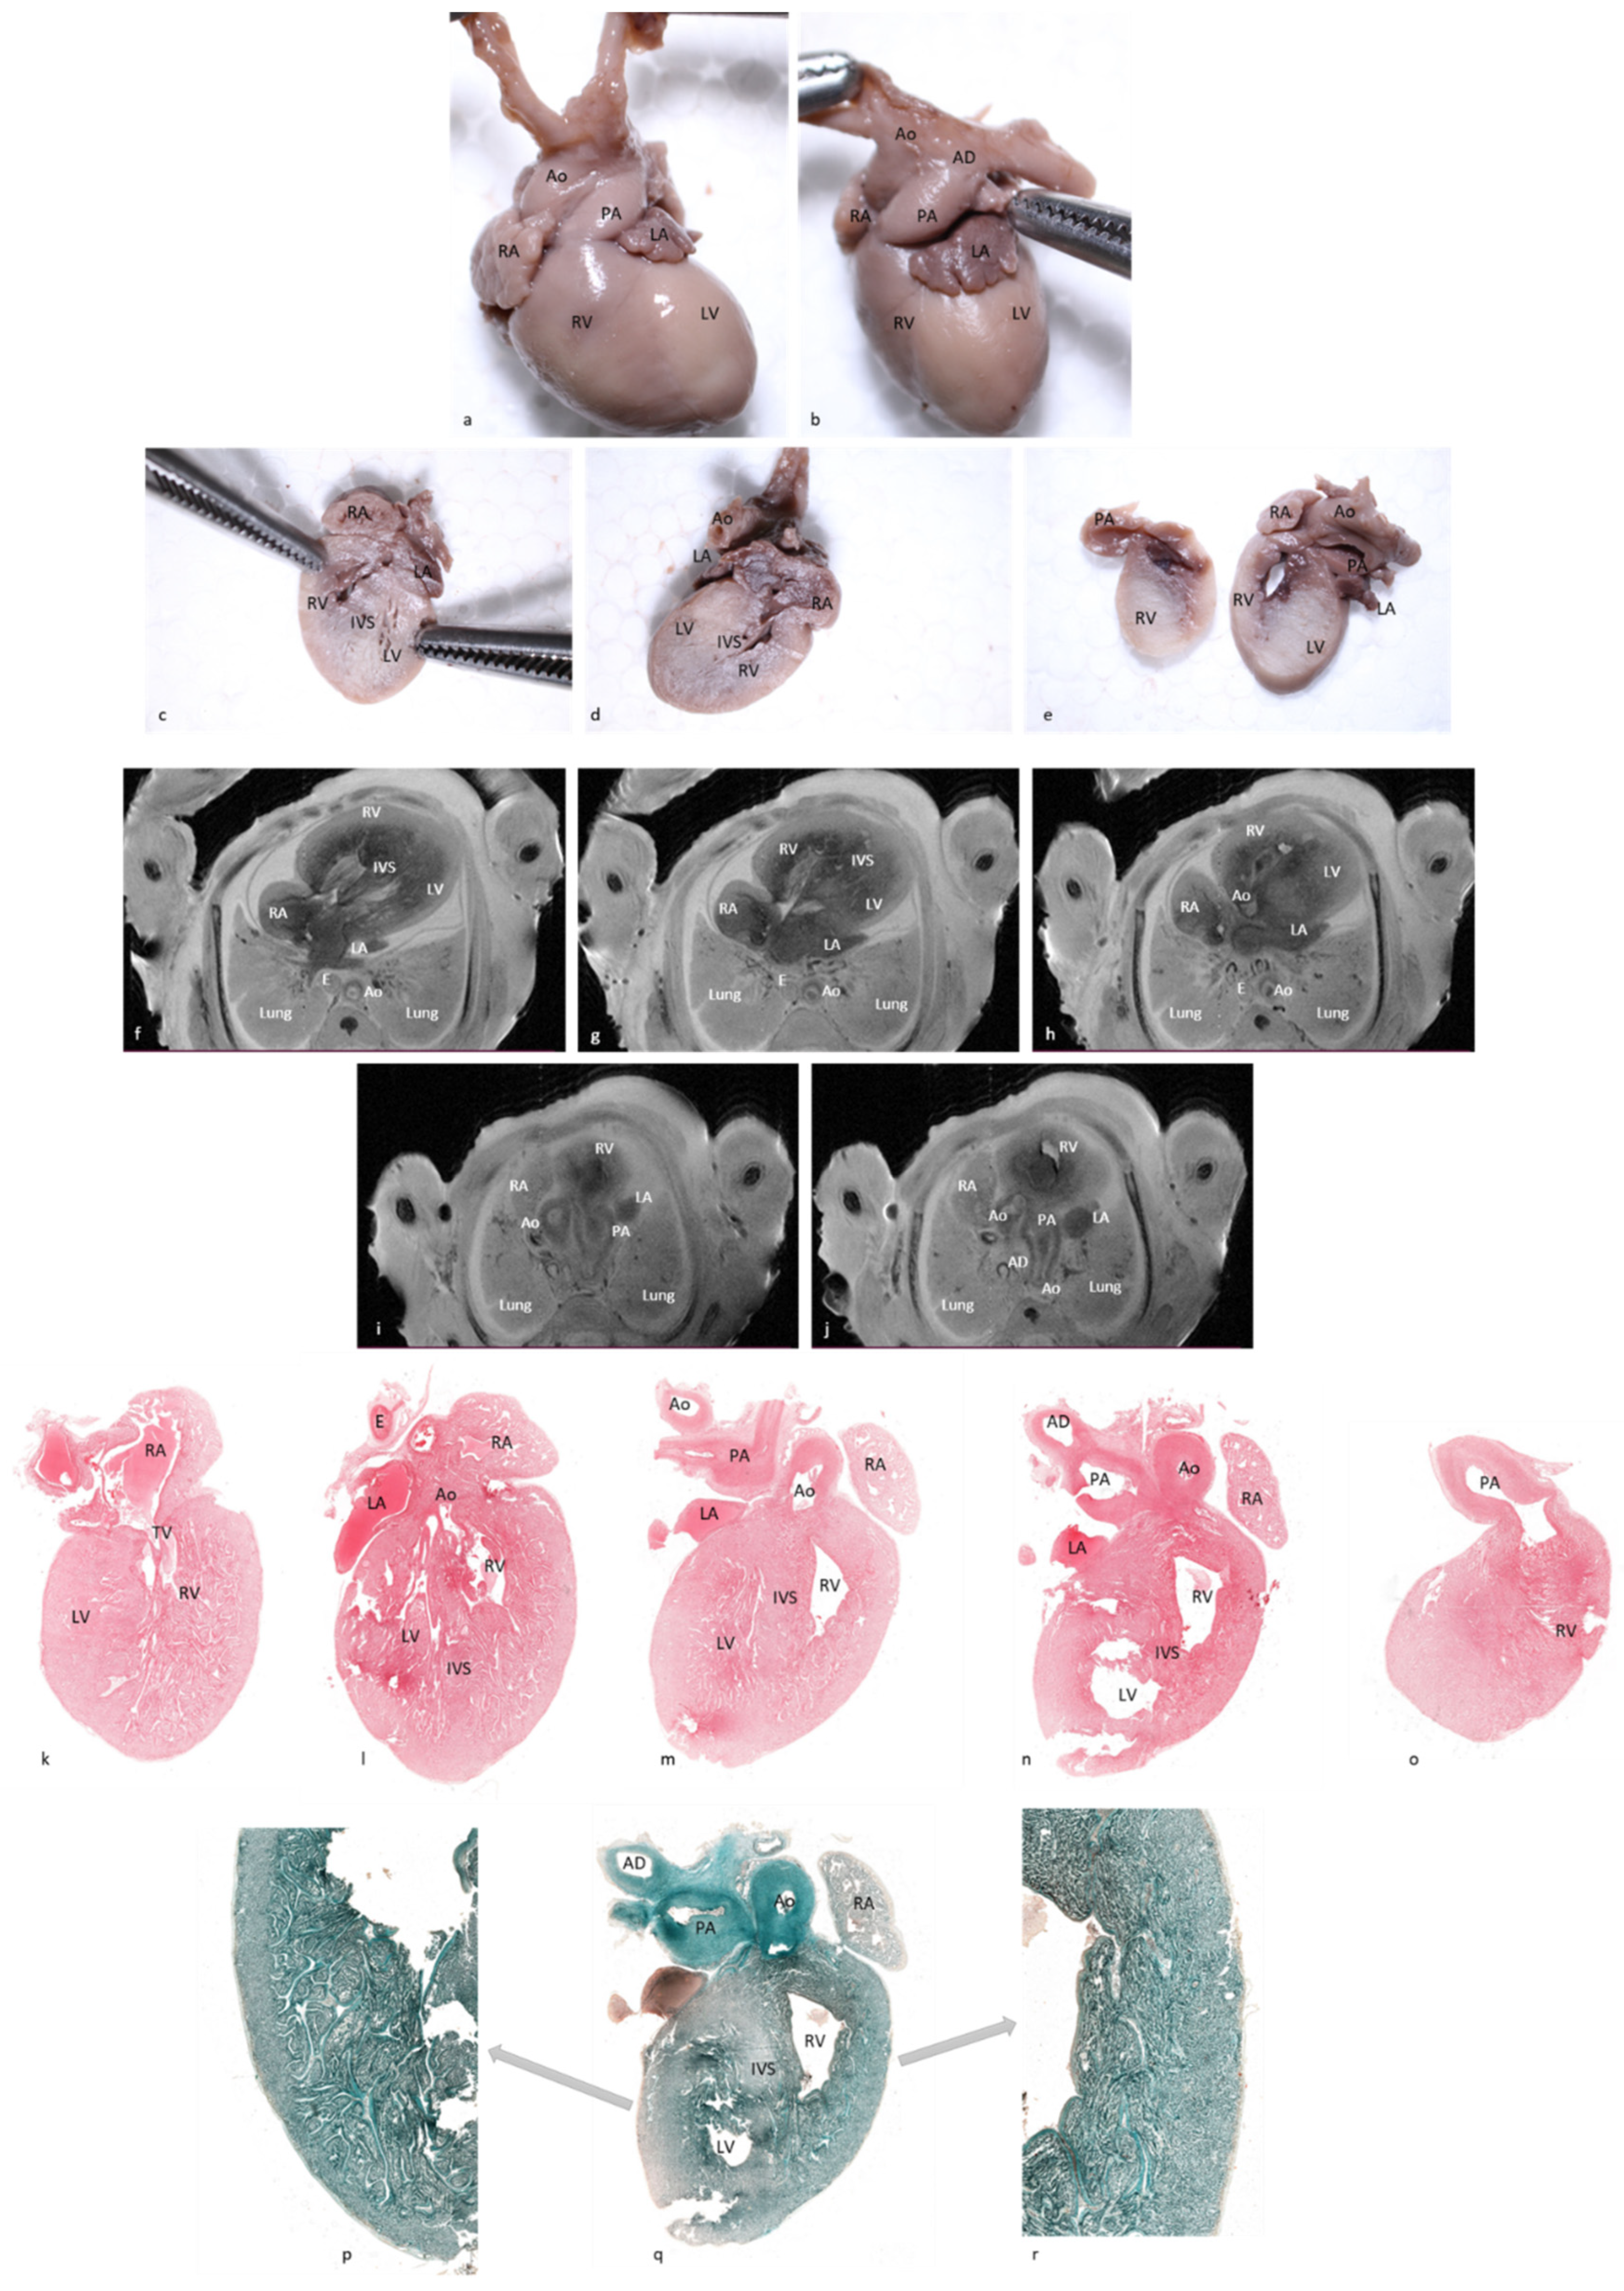

Figure 1 depicts the fourteen cardiac items evaluated.

The data set included 168 structures (12 cases × 14 structures for each case). All items included were properly visualized using pm-MRI.

After external examination, two longitudinal sections were performed parallel with the diaphragmatic surface of the heart, as depicted in

Figure 2a,b. The first section was performed through both ventricles and both atria, obtaining a four-chamber view. The second section was performed parallel to the first through the infundibulum and pulmonary artery valve. All obtained sections were processed using a vacuum infiltration processor, namely Tissue-Tek VIP 5 Jr (Sakura, Alphen aan den Rijn, The Netherlands), and embedded in paraffin blocks.

Due to inclusion and sectioning techniques, microscopic sections of the inferior side of the heart were a mirrored view of the macroscopy because the section was flipped over during the paraffin embedding. For the other two sections, the left–right sides corresponded to the external cardiac view, as depicted in

Figure 2c–h and

Figure 3, hence, after sectioning, they were included without flipping.

The pathologic four-chamber examination protocol is described schematically in

Figure 4.